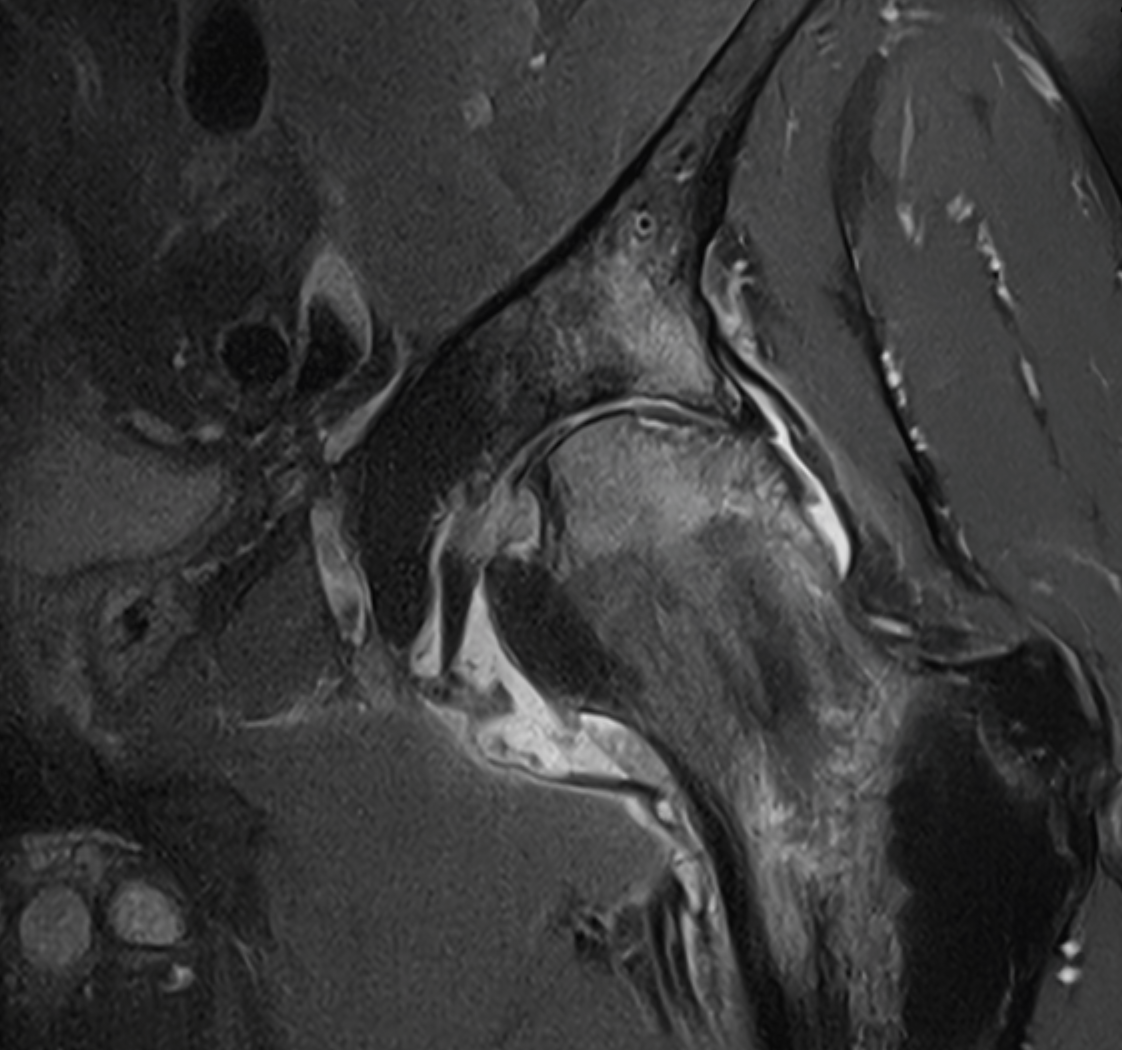

3. Avascular Necrosis (AVN) of femoral head